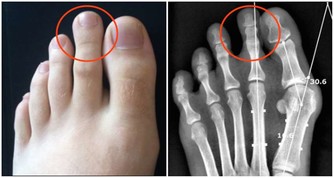

2、菸酒

酒精對胃黏膜有較大的損害,人們在吸煙時候,煙霧中的有害物質,溶解並附著在口腔、咽喉部,隨吞嚥進入胃內,這些有害物質對胃黏膜也有很大損害。因此,急、慢性胃炎患者,一定要戒除菸酒,以免加重病情,甚至造成惡性變。吸煙喝酒與肺癌,胃癌的發生密切相關。